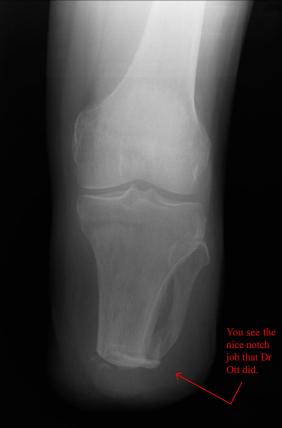

On May 30th 2007 exactly 2 years and 2 days from the day that Liam had his skydiving accident, doctor Ott removed the lower part of Liam’s left

leg using what is described as an Ertl procedure. The Ertl procedure results in a residual limb that is stronger and has a greater ability to load bear.

It is expected that Liam’s fatigue will be greatly reduced as a result of the Ertl procedure. The X-Rays show the best details associated with the Ertl

procedure. It can clearly be seen that a piece of bone (from the fibula) has been used to bridge the gap between tibia and fibula. What can not be seen

is the amount of tissue and muscle that was used (found normally in the lower part of the limb) to form a sort of pocket surrounding the remaining bone.

Through the great efforts of doctor Ott and Owen from the Artificial Limb Specialist Group, Liam has been given good responses regarding his rate of

healing and his prognosis for a great recovering. At this stage Liam is using sleeves that help reduce swelling and shape the stump so that it best fits the

prosthetic limb that will be used by Liam to walk.

Putting a little time between the amputation and Liam's acclimation to the prosthetic, these images are of the most recent x-rays of Liam's

left leg, which looks great and is able to support full body weight. Liam's is almost off all of the drugs and able control the residual pain. As can

be seen in the x-rays, Dr Ott did a great job with providing Liam with a load barring bone structure. The images of Liam's 2 prosthetic legs provide